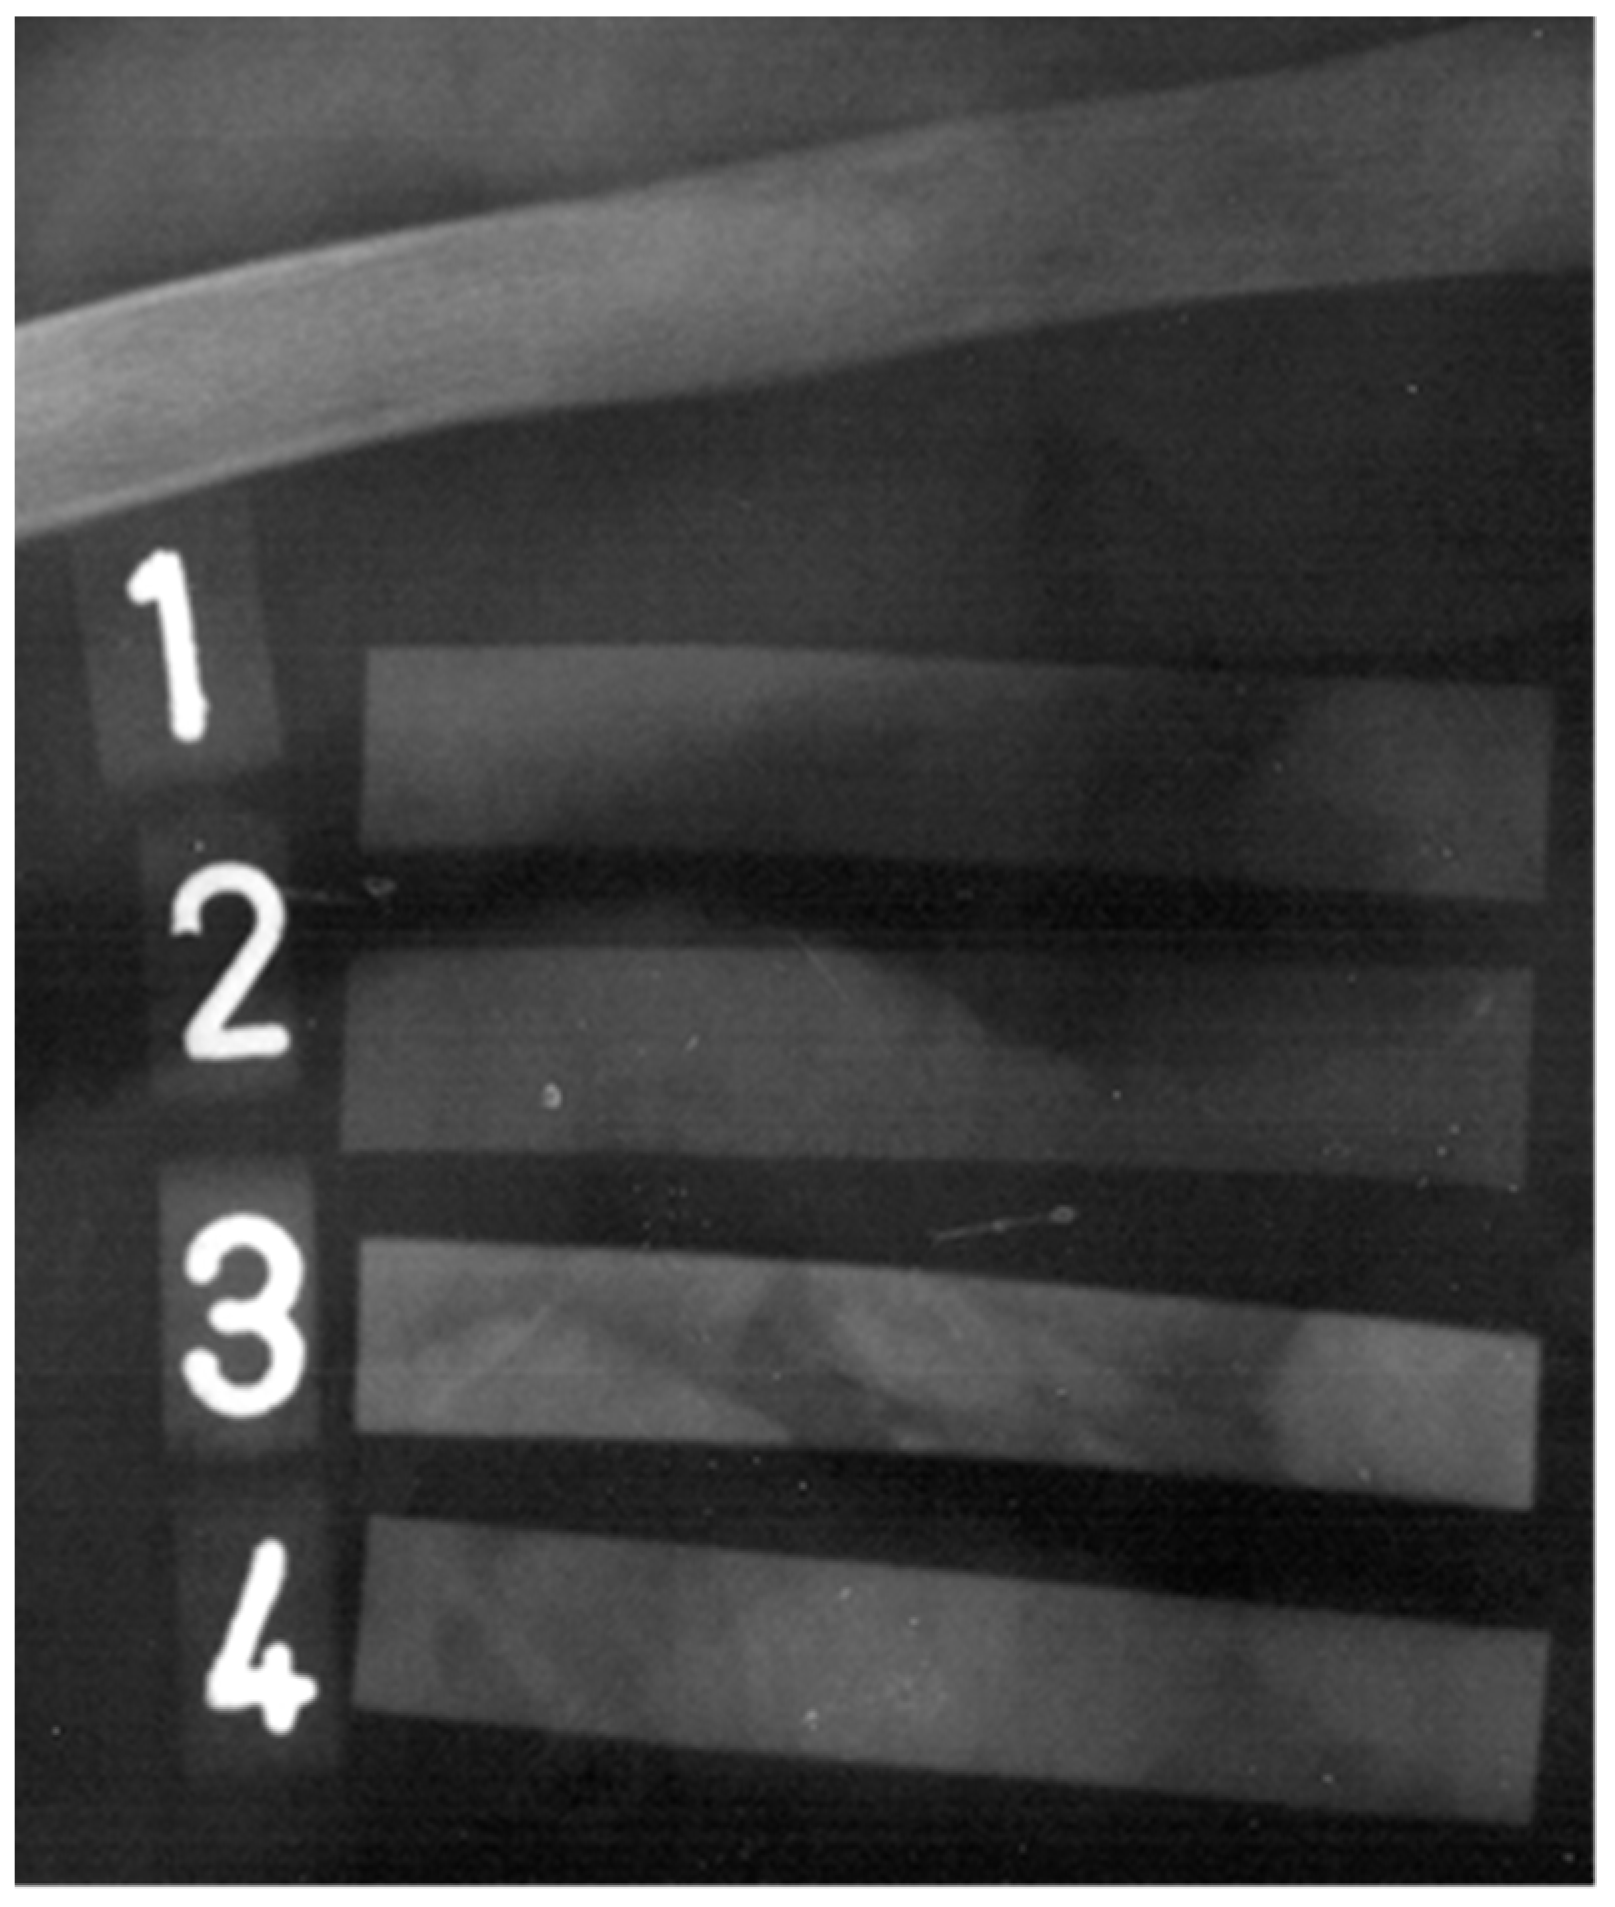

3.5. Radiopaque Detection